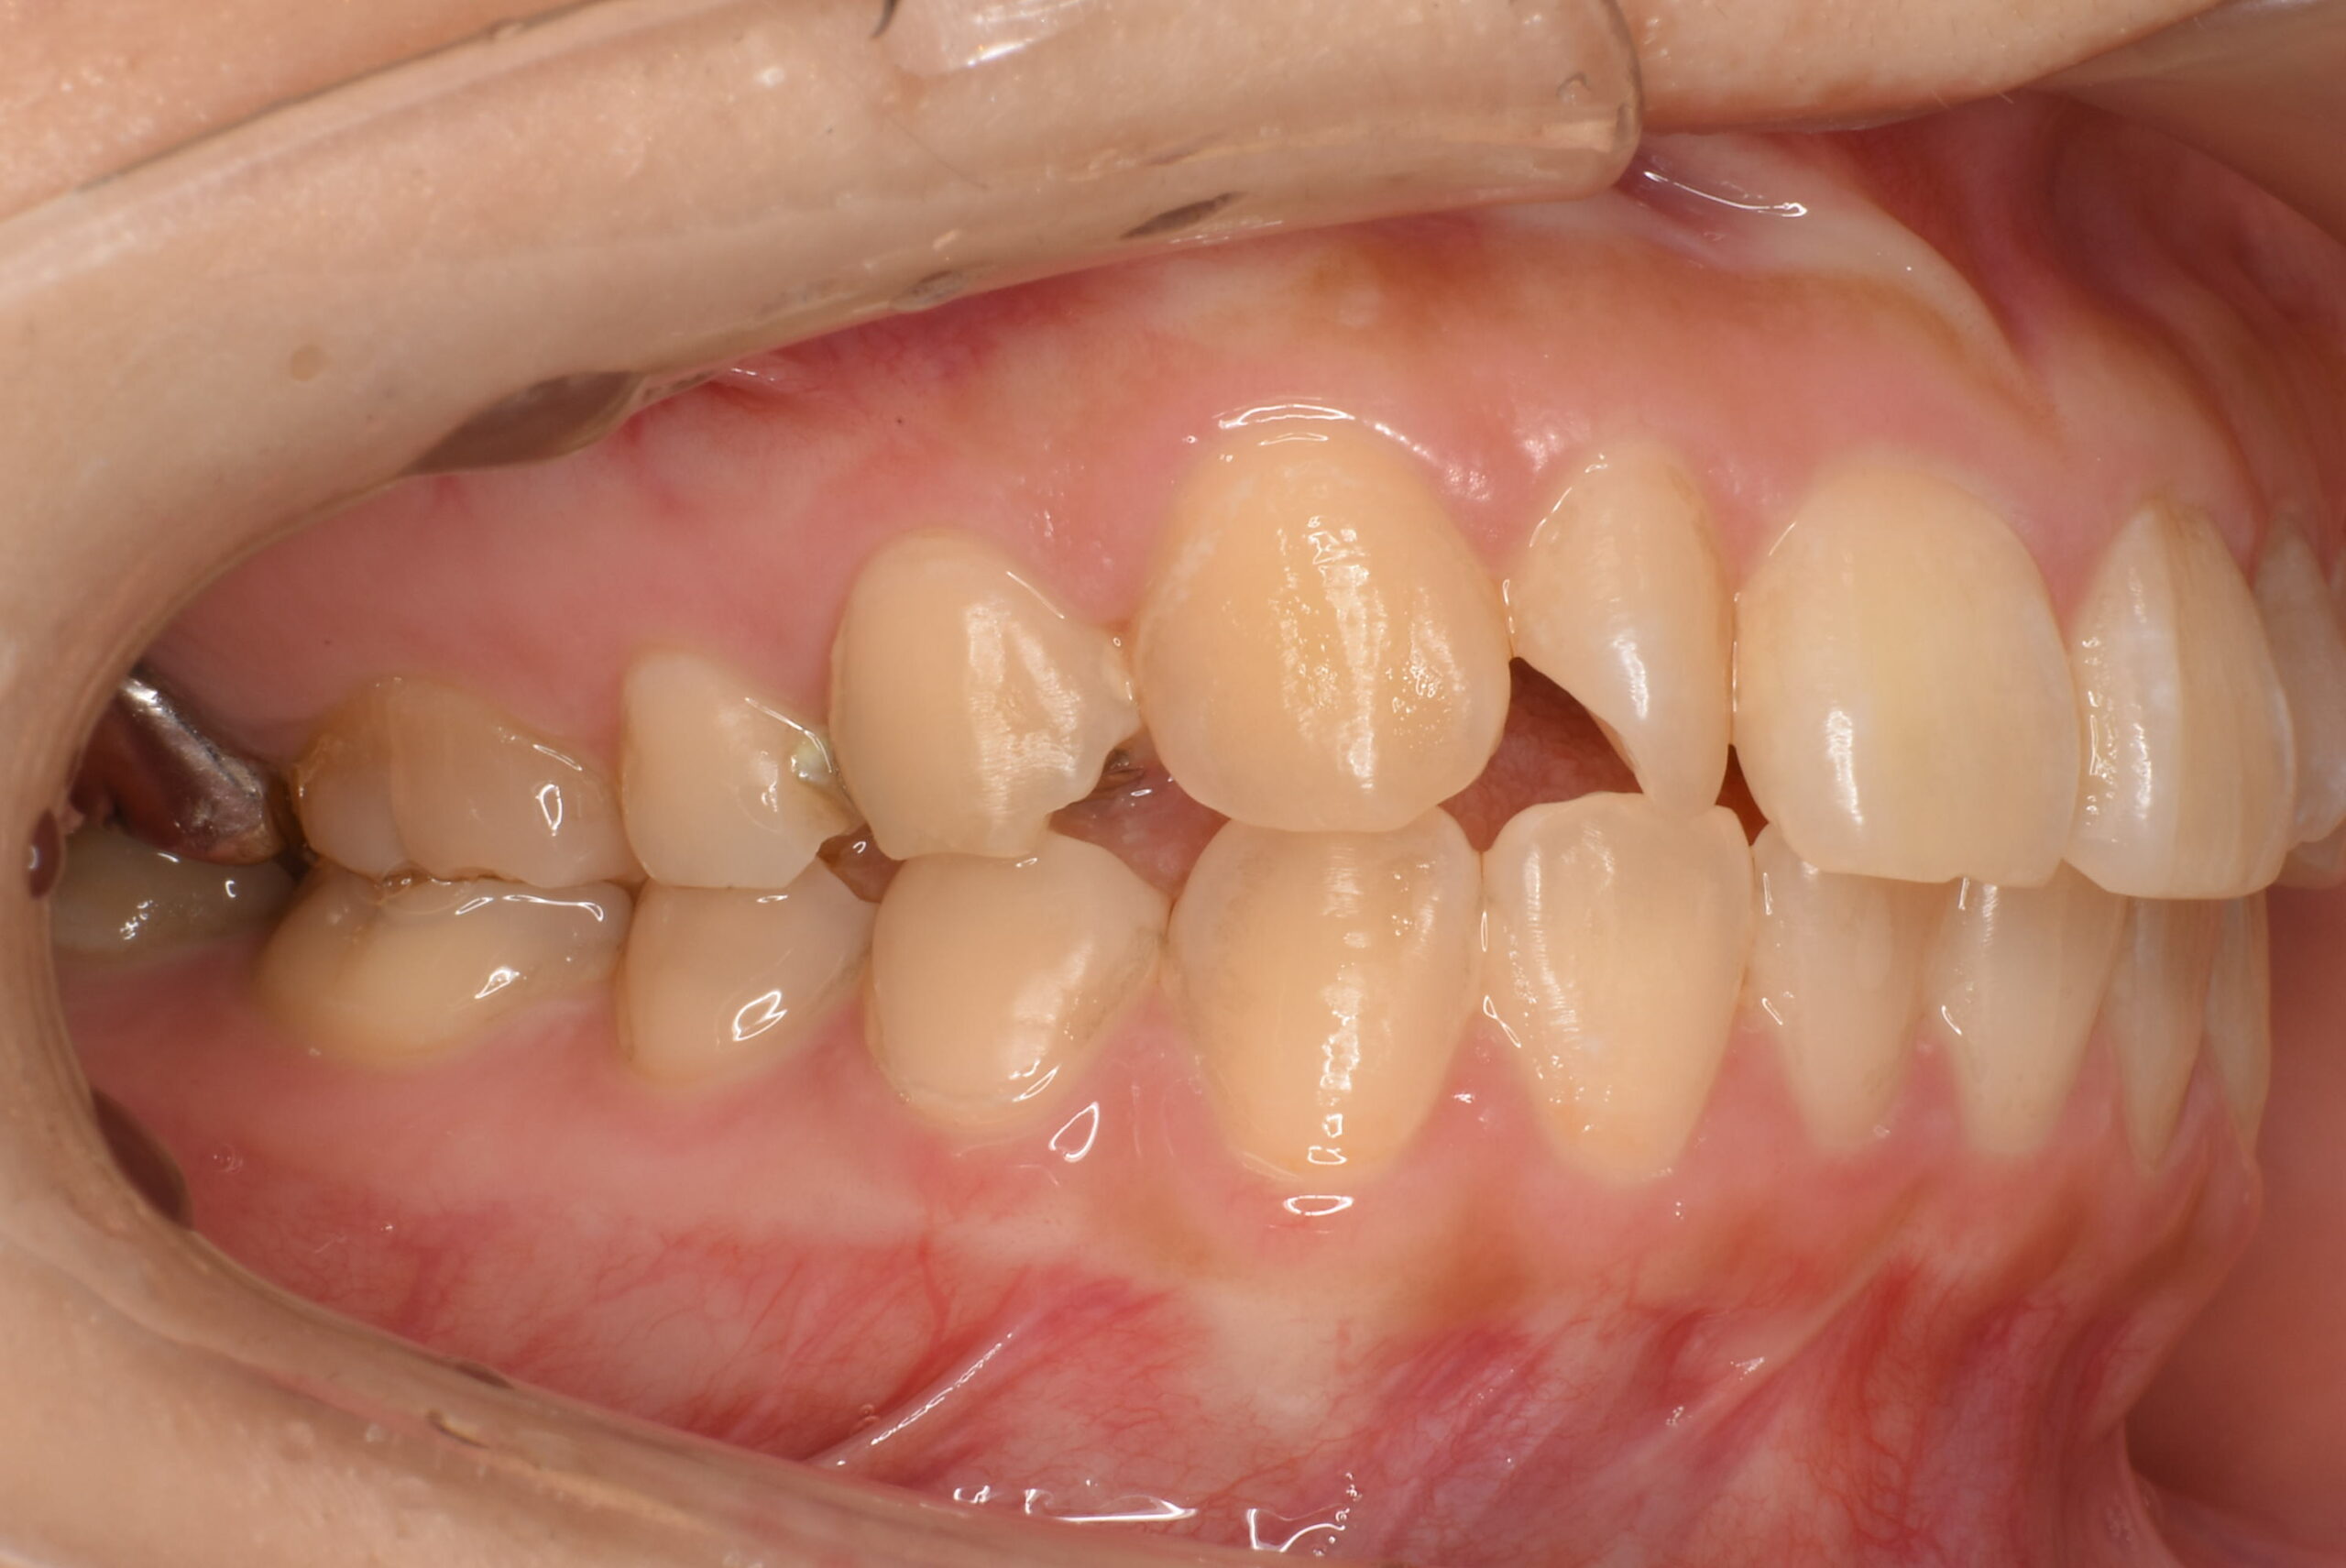

治療前_右側方

| 治療内容 | 不揃いな歯並び(叢生)や、歯のガタガタ・デコボコが気になることを主訴に来院されました。 目立ちにくい装置での治療をご希望されたため、マウスピース型矯正(インビザライン)による矯正治療を行いました。 治療途中、上顎左右にカリエスが認められたため、矯正治療と並行してCR修復(コンポジットレジンによる虫歯治療)を行いました。 2021年12月にお引っ越しのご予定があり、2022年3月までの治療終了を希望されていたため、治療計画を調整しながら進行管理を行い、予定期間内での治療完了を目指しました。 |